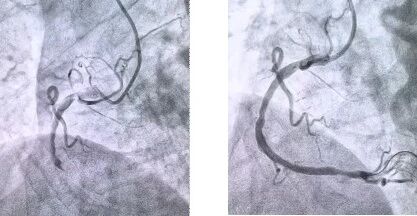

患者抵達(dá)醫(yī)院后,簡化掛號、繳費等中間環(huán)節(jié),迅速溝通病情,需要緊急介入治療,獲得家屬同意,立即送至導(dǎo)管室。造影顯示其右冠狀動脈中段完全閉塞,醫(yī)生迅速實施血栓抽吸,球囊擴(kuò)張和藥物洗脫支架植入術(shù)。36 分鐘后,閉塞血管恢復(fù)正常血流,吳大爺?shù)难獕骸⑿穆手饾u平穩(wěn),胸痛癥狀明顯緩解。術(shù)后三天,他便轉(zhuǎn)入普通病房進(jìn)行康復(fù)訓(xùn)練,重拾健康生活。